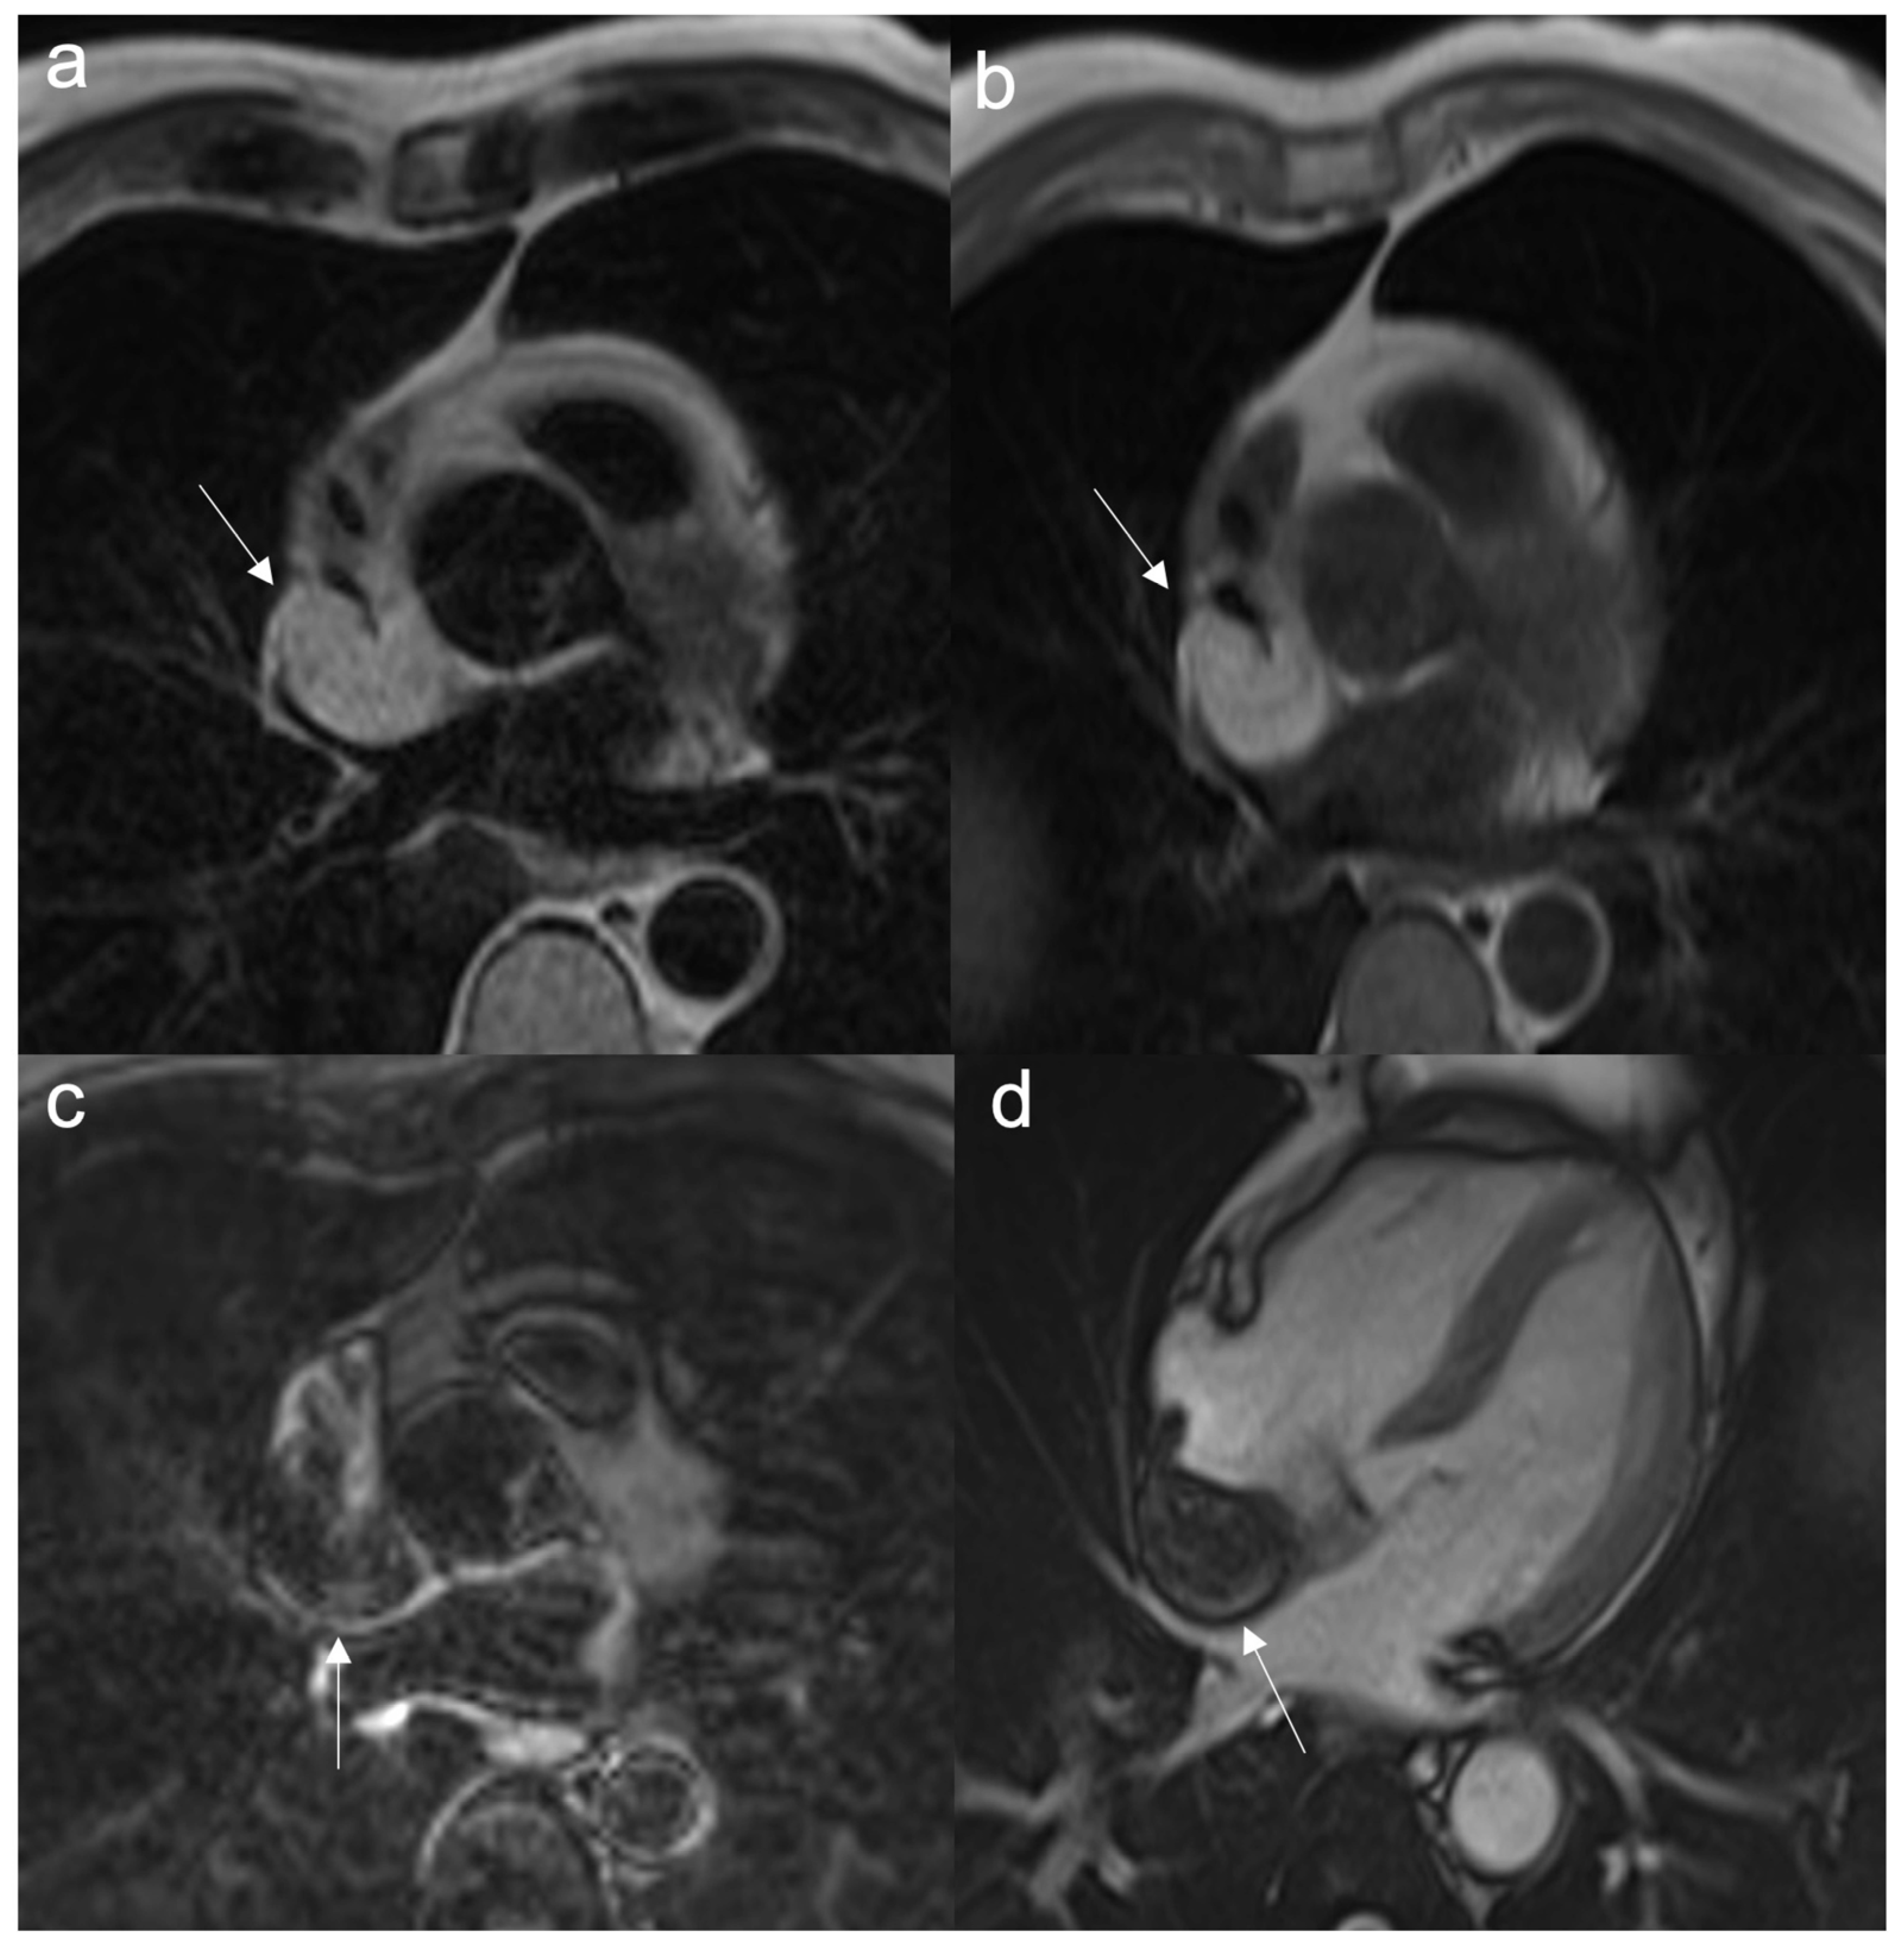

7.1.2. Cine Sequences

- Two-chamber (2CH SSFP): along a plane passing between the center of the mitral-tricuspid annulus and the apex of the left and right ventricles, depending on the location of the tumor.

- Four-chamber (4CH SSFP): along an image plane passing through the center of the left ventricular cavity and the right ventricular costophrenic angle

- Three-chamber (3CH SSFP): along a plane passing between the aortic and mitral annulus and the apex of the left ventricle

- Short-axis (SAX SSFP) acquisitions are acquired along an image plane perpendicular to the interventricular septum, passing through both ventricles and sometimes the atria.

- To evaluate motion and myocardial contraction

- To assess border, size, and location

- Very useful for stable anatomical relationships of the mass with myocardium (intramyocardial or pedunculated) and with adjacent structures

- To evaluate mobile masses, such as atrial myxomas or papillary valve fibroelastoma

- To reveal pericardial effusion

- Cardiac valve function and visualization of stenotic or regurgitant flow jets